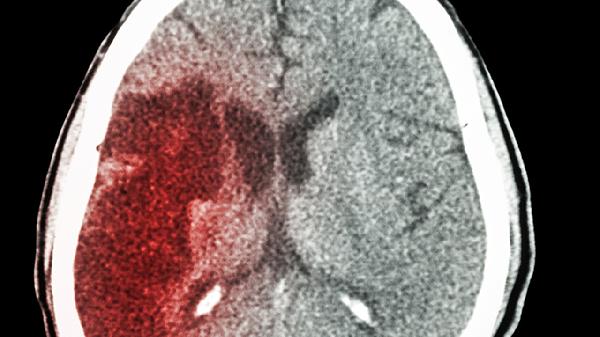

长期头昏脑胀患者应注意保持规律作息,每日睡眠时间不少于7小时,避免过度劳累。饮食上适当增加富含优质蛋白和维生素B族的食物,如鱼类、全谷物等。建议每周进行3-5次中等强度有氧运动,如快走、游泳等。若症状持续2周以上不缓解,或出现剧烈头痛、意识障碍等警示症状,须立即就医排查脑血管病变等严重疾病。日常可进行颈部放松操、深呼吸训练等帮助改善脑部血液循环。